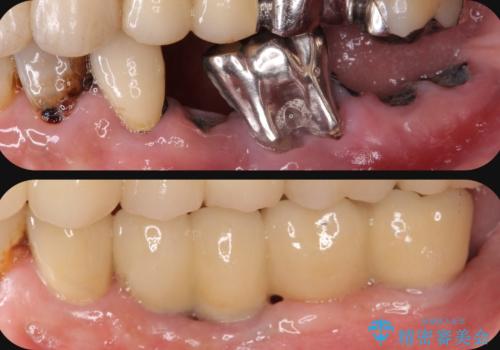

- 虫歯が多発し、多数失ってしまった歯の審美性回復・機能回復を計画します。

多数の歯が失われておりブリッジは行えないような状況で、インプラント治療か入れ歯治療かを提案しインプラント治療を希望・選択されました。

連続した多数の歯の機能・審美回復にブリッジは設計上治療の手段になり得ない場合があります。

残された選択肢は入れ歯・インプラントになりますが審美性・咬合機能の回復度・快適さ・残存歯への負担は雲泥の差となります。